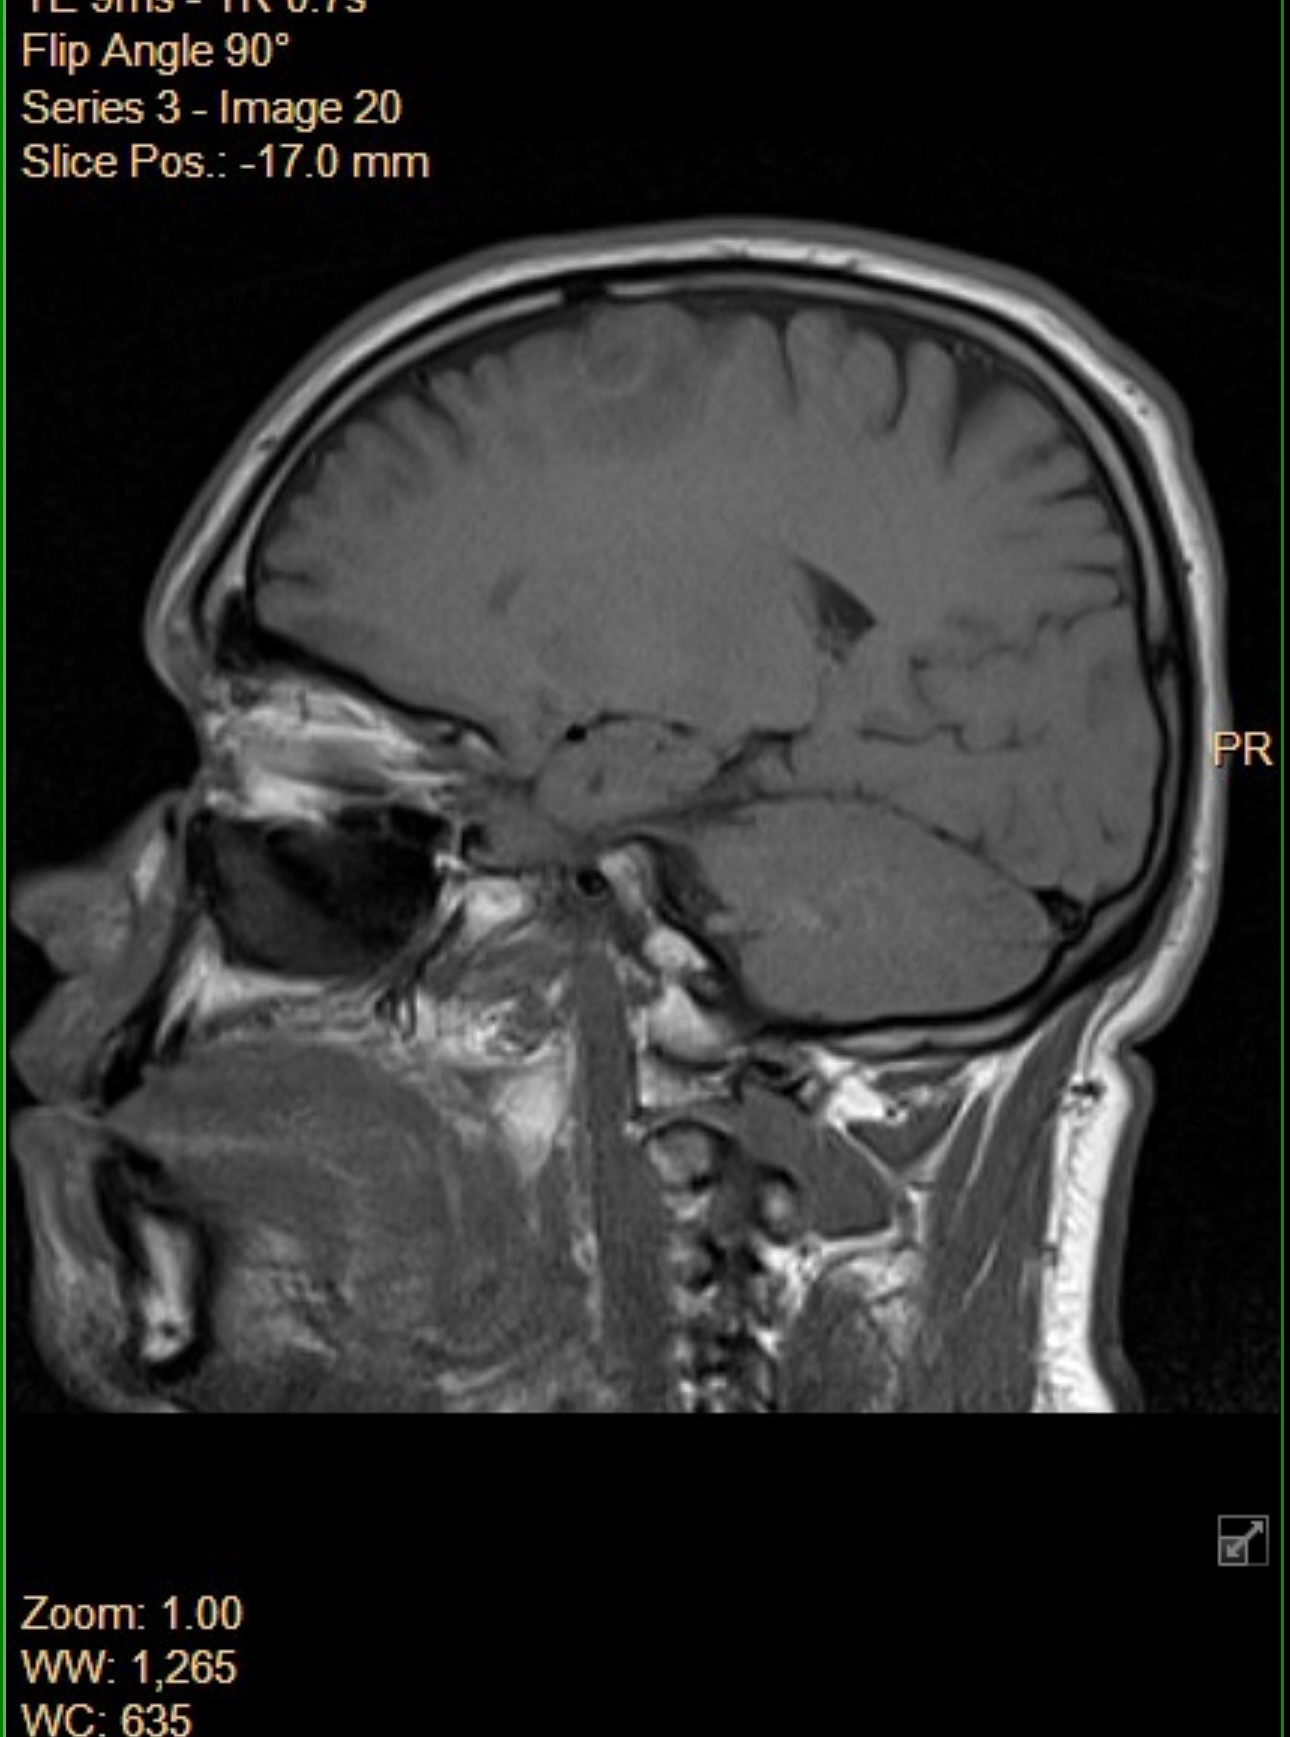

2 years ago, I was diagnosed with Ependymoma Grade 2, a rare type of brain tumor and cancer. Mine is RELA fusion-positive, a particularly aggressive subtype that falls under what’s known as high-grade central nervous system tumors (HCC). Hearing those words from my doctor turned my whole world upside down.